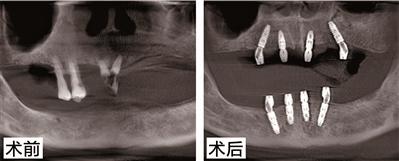

陳伯今年76歲了,也是德國種植牙技術(shù)的親身體驗者之一。他之前患有牙周病,牙齒全口缺失,在醫(yī)生的指導(dǎo)下采用了德系A(chǔ)ll-on-N種植技術(shù)和種植技術(shù),種牙到現(xiàn)在3年了,牙齒依然堅固如初。為此,陳伯感嘆道:“缺牙這么多年,沒想到是柏德幫自己實現(xiàn)了多年的愿望。我記得種完牙當(dāng)天就能正常吃飯。一把年紀(jì)還能再次享受口福,這種感覺真好?!睋?jù)悉,百蟹宴當(dāng)天,陳伯將應(yīng)邀分享種牙感受,并與現(xiàn)場觀眾比拼吃大閘蟹,展示種牙后的果。種植牙PK大閘蟹,究竟誰能勝出呢,我們拭目以待!

針對陳伯的種牙情況,柏德口腔天河院長薛啟明表示,All-on-N種植技術(shù)和種植技術(shù)可以說能很好地解決多顆牙缺失或者全口無牙問題,尤其是對于上了年紀(jì)又怕痛的缺牙患者。電腦三維模擬成像技術(shù)能在手術(shù)前,地計算種植點位、植入角度和深度,再通過3D種植導(dǎo)板植入,避開神經(jīng)系統(tǒng)和血管,實現(xiàn)種植。整個手術(shù),在麻醉儀的幫助下,患者幾乎沒有任何不適。德系A(chǔ)ll-on-N種植技術(shù)還有一個好處就是,只需要花少量的錢,就能恢復(fù)整口牙的咬合果,這對患者來說無疑是實惠的。